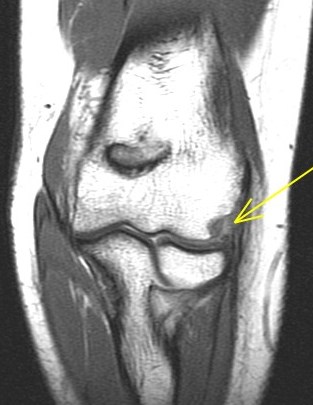

21 y/o F s/p wrestling injury. R/O acute radial head fracture.

Complex combination of valgus and varus stresses, probably a subluxation. Note the tear of the posterior lateral capsule just behind the ligamentous origin on the pdfs coronal. Patient should have posterolateral rotatory instability (PLRI). Also had extensor tendon strain with partial tear, trabecular injury of the coronoid process and of the humeral trochlea. Reference article.

Tear of combined origin of the lateral ulnar collateral ligament and radial collateral of elbow (RID2043)(RID2035)